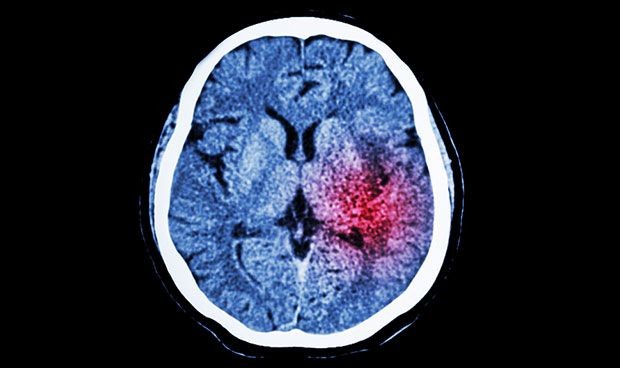

Imagen obtenido por TAC de un ictus isquémico.